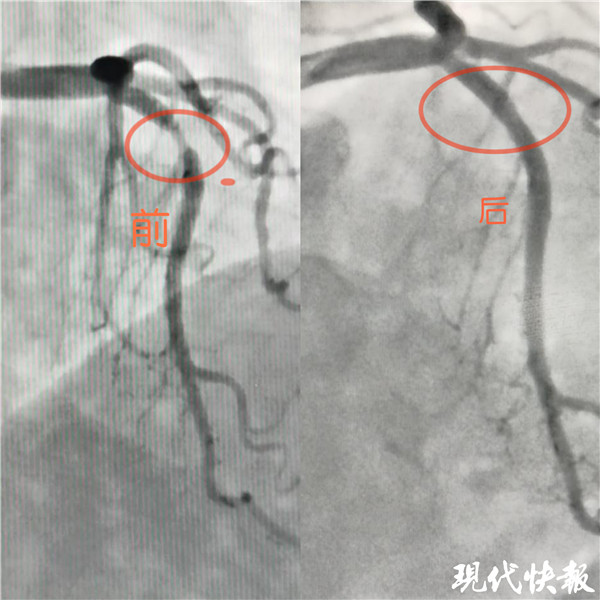

記者了解到,入院后完善冠狀動(dòng)脈造影檢查示,張女士LM正常,LAD近段血管90%狹窄, LCX及RCA未見狹窄?;窗彩幸辉盒膬?nèi)科介入治療團(tuán)隊(duì)嚴(yán)格把握適應(yīng)癥,和患者及家屬溝通后,于LAD病變處植入一枚藥物可吸收支架,術(shù)后血管內(nèi)超聲檢查提示支架貼壁良好。